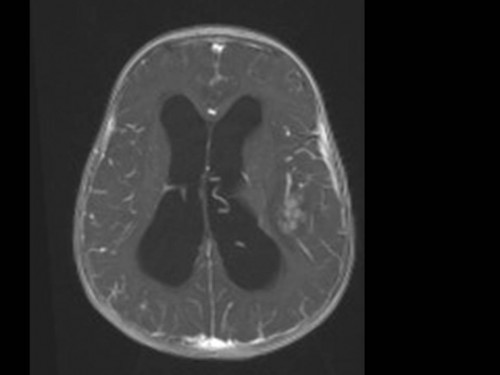

10 Monate altes Mädchen. Der Kinderarzt stellt fest, dass das kleine Mädchen einen recht großen Kopfumfang hat, nicht mit den Augen fixiert und anscheinend auch nicht richtig sehen kann. Damit bestätigt er die größten Befürchtungen der Eltern, denen in den letzten Wochen aufgefallen war, dass ihre Tochter nach keinem Spielzeug mehr greift und sie nur dann anlächelt, wenn sie zu ihr sprechen.

Bildgebung - MRT